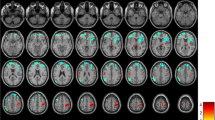

The amplitude of the activity was higher (p < 0.05) in all examined networks in the 0.08–0.04 Hz frequency range and in the lateral visual network also in the 0.16–0.08 Hz frequency band (Fig. 1 ) in the MWA group. There were no other significant results in any other frequency bands or in case of the non-filtered data.

All of the investigated network ((a) medial visual, (b) lateral visual, (c) default mode, (d) right attention, (e) right attention) showed higher amplitude in the 0.08–0.04 Hz frequency range in MWA compared to MWoA. The images on the left depicting the resting state networks are thresholded at p < 0.5 and overlaid on the standard MNI_152 brain. The boxplots depicting the amplitude of the activity of the networks in the 0.08-0.04 Hz frequency range. The central mark is the median, the edges of the box are the 25th and 75th percentiles, the whiskers extend to the most extreme datapoints